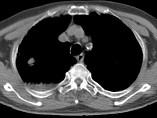

问题 男,76岁,气喘数年,胸痛1个月余,结合影像图像,选择最可能的诊断 ( )

选项 A.右上肺结核球 B.肺间质纤维化 C.右上肺瘢痕癌 D.右上肺错构瘤 E.右上肺肉瘤

答案 C